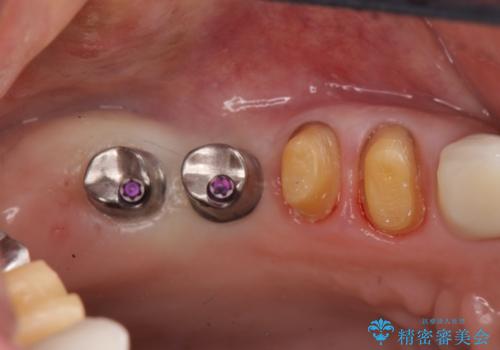

親知らず、ブリッジを抜去・撤去しインプラントを用いた咬合機能回復を行っていくこととしました。

- 123.2万円(インプラント×2・チタンカスタムアバットメント×2・ジルコニアクラウン×4・仮歯×4)費用は治療当時の料金となります

しっかりと噛めるようになったと同時に歯ブラシもしやすくなり、食生活がまた楽しめるようになったと喜んでいただくことができました。